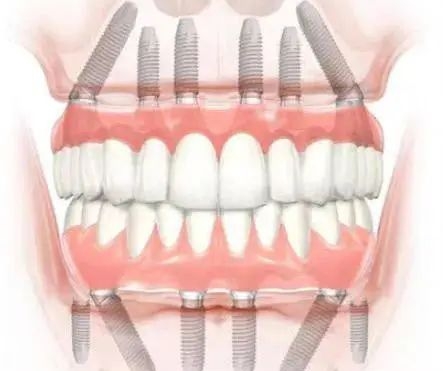

刘本义院长擅长各类种植牙项目,无论是常规单颗、多颗种植,还是高难度的all-on-4、穿颧穿翼种植,都能稳准完成,技术覆盖全场景缺牙修复需求。